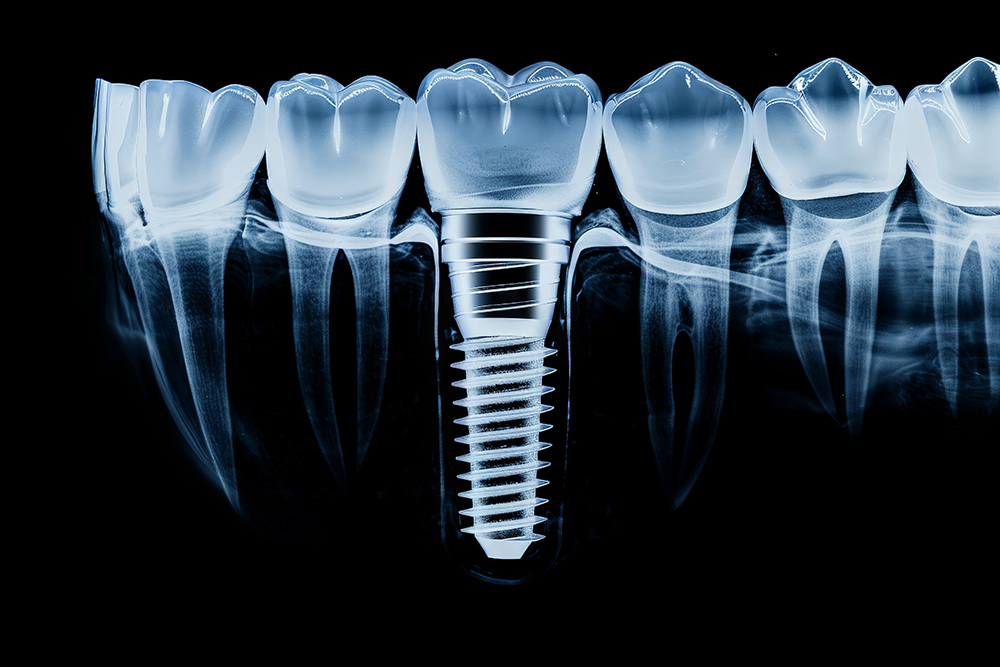

임플란트 시술 전, 의사는 환자와 초기 상담을 진행하며 환자의 요구사항과 건강 상태를 확인합니다. 이때 X-ray 촬영, 3D CT 스캔 등을 통해 환자의 구강 구조를 면밀히 분석합니다. 이 과정을 통해 시술 계획이 구체적으로 잡히며, 필요시 추가적인 치료(예: 뼈이식)가 논의될 수 있습니다.

본격적인 임플란트 식립 과정에서는 치조골에 인공치아 뿌리(임플란트)를 심습니다. 이 과정은 국소마취를 하며, 수술 시간은 보통 한 개당 30분에서 1시간 정도 걸립니다. 수술이 끝나면 잇몸을 봉합하고, 임플란트가 뼈에 완전히 결합될 때까지 기다려야 합니다.

임플란트가 뼈와 단단히 결합하는 과정을 '골유착'이라고 부릅니다. 이 기간은 약 3개월에서 6개월이 필요하며, 뼈 상태에 따라 다를 수 있습니다. 골유착이 잘 이루어져야만 임플란트가 안정적으로 자리잡고, 정상적인 기능을 수행할 수 있습니다.